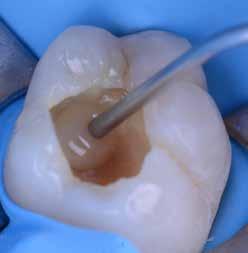

Az 53 éves hölgy páciens jobb felső 6-os fogában látható amalgámtömés cseréje volt a cél. A tömés mellett secunder caries és az amalgám következtében létrejött mesialis zárólécen áthaladó repedés, továbbá mesialis caries figyelhető meg (1. ábra). El kellett kerülni, hogy a tömés kifúrásakor az amalgámtörmelék a páciens szájába kerüljön, esetleg ebből valamennyit lenyeljen, a kezelés első lépésként kofferdám izoláció került fel a jobb felső kvadránsba (2. ábra). A kapocs a 1.7 fogra került, ezzel kényelmesen helyet teremtett a későbbiekben felkerülő matricarendszernek. Az egyszerre több fog izolálása lehetővé teszi, hogy a szomszédos fogak referenciául szolgáljanak a restauráció felépítése közben.

A régi amalgámtömés eltávolítását követően caries indikátor segítette a carieses laesio megfelelő kitisztítását a pulpa expozíciója nélkül. Ezután kerülhetett sor az ideális üregdesign kialakítására, továbbá a zománcszélek finírozására (3. ábra) Az approximális box megnyitása során az alátámasztatlan zománcprizmák eltávolításra kerültek, ezzel is csökkentve a secunder caries képződés veszélyét. Az így kialakuló forma elősegíti a matrica megfelelő adaptációját, végül pedig az approximális box határainak a hozzáférhetőségét, így finírozás során ez jobban kontrollálható és polírozható.

A Palodent V3 matricarendszer felhelyezését követően a zománc 10 másodperces szelektív savazása, majd lemosása és leszárítása után történt a kavítás bondozása Prime & Bond Universallal.

Kulcslépés: a II. osztályú üreget a matricarendszer segítségével I. osztályúvá lehetett átalakítani.

A pontosabb széli záródás érdekében célszerű a matrica illesztési határába némi folyékony kompozitot felvinni (NeoSpectra ST flow A2), majd megvilágítás nélkül a zárólécet paszta kompozittal (NeoSpectra STHV A2) felépíteni, miközben a kifolyó fölösleges folyékony kompozit eltávolításra kerülhet. Így ki lehetett használni és kombinálni a két különböző konzisztencia előnyeit.

A polimerizációt követően kerülhet sor a matricafeszítő gyűrű, valamint a matrica eltávolítására. A Palodent V3 fülekkel ellátott matrica kialakításának és a speciális PinTweezers csipesznek hála, a feszes kontaktpont ellenére a matrica könnyedén eltávolítható. Az éket viszont a kezelés végéig

célszerű bennhagyni, elkerülve egy esetleges nemkívánatos vérzést (4. ábra)